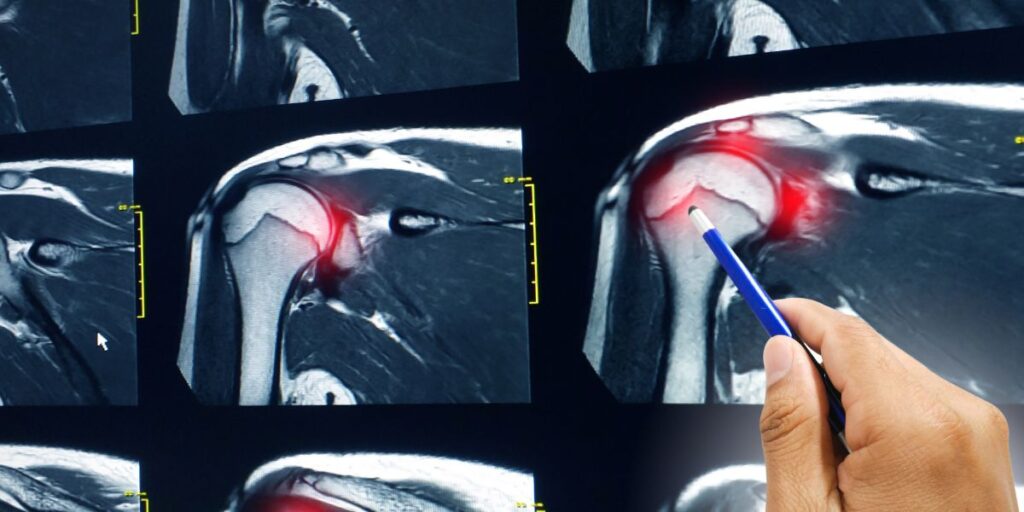

• Risonanza Magnetica: fondamentale per un’analisi dettagliata delle strutture interne dell’articolazione.

Esami Diagnostici Utilizzati dallo Specialista in Chirurgia della Spalla

Per una valutazione completa, lo specialista in chirurgia della spalla del Poliambulatorio S-Medical Group di Sora può avvalersi di diversi esami diagnostici, tra cui: